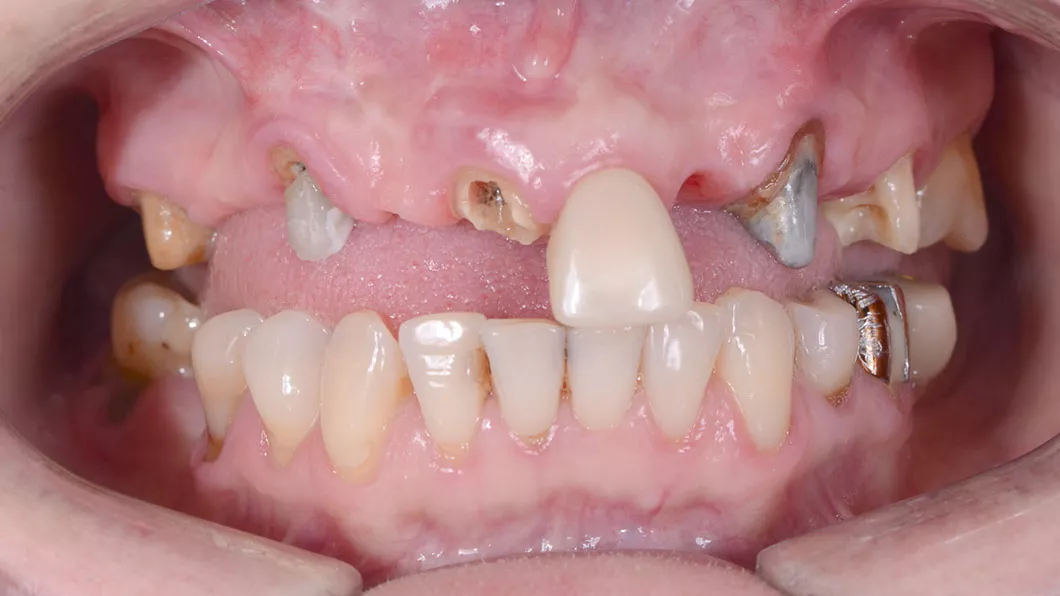

Пациентка обратилась с жалобами на неудовлетворительный внешний вид старых коронок и мостовидных протезов, а так же дискомфорт и боль при жевании, в связи со значительной подвижностью конструкций.

Лечение: снятие старых коронок и мостовидных протезов. Удаление зубов, не подлежащих лечению. Костная пластика и десневая пластика. Установка 3-х зубных имплантатов на верхней челюсти и 2-х имплантатов на нижней челюсти.

Протезирование: цельнокерамическими мостовидными протезами и коронками на зубах, имплантатах.

После снятия старых коронок

Установка зубных имплантатов

Вид перед установкой керамических коронок на зубах и зубных имплантатах

Процесс установки цельнокерамического мостовидного протеза с опорой на имплантаты

Вид после фиксации керамических конструкций